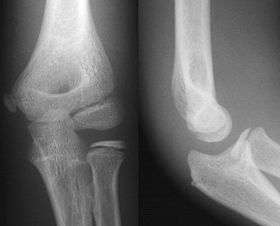

![]() AP and Lateral Elbow X-Ray | |

- Elbow - AP and Lateral. Radial head projections available on request